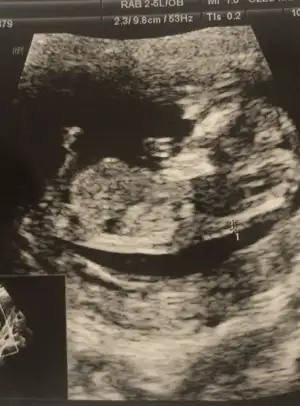

Bence erkek gibiKızlar sizce cinsiyet olarak ne hissettiniz?Göstermedi

Erkek

Ya kız gibi hissettim nedenseKızlar sizce cinsiyet olarak ne hissettiniz?Göstermedi